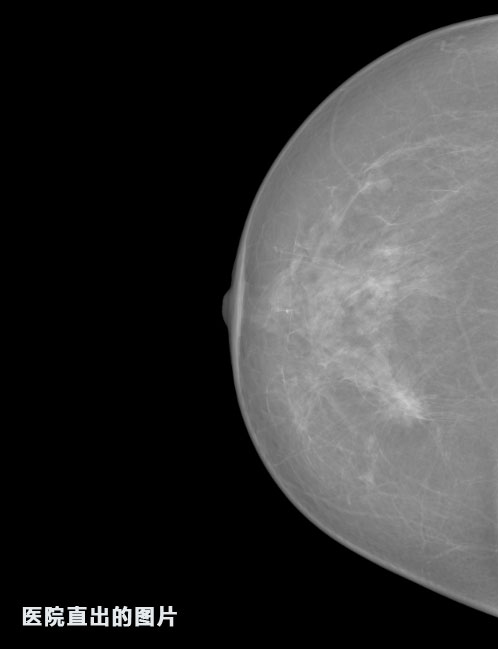

英特健康A(chǔ)I深度學(xué)習(xí)醫(yī)療圖像識別系統(tǒng)案例_乳腺

01.jpg

02.jpg